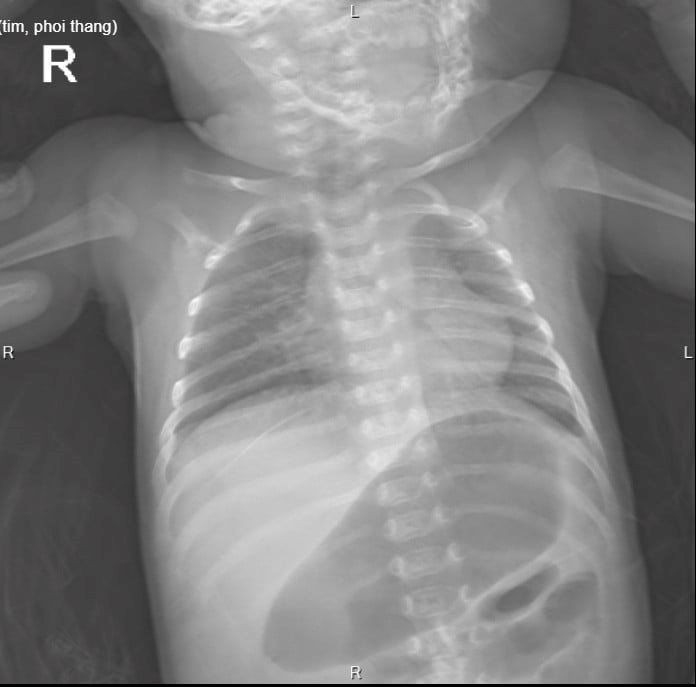

Trên phim chụp X-quang của bệnh nhi cho thấy có hình ảnh thoát vị hoành trái, các tạng thoát vị chiếm toàn bộ khoang màng phổi, không còn nhìn thấy hình ảnh nhu mô phổi trái, tim và trung thất bị đẩy lệch sang phải chèn ép một phần nhu mô phổi phải, đồng thời xét nghiệm RSV cho kết quả dương tính. Trẻ được chẩn đoán thoát vị hoành trái nghẹt, suy hô hấp viêm phổi nặng do RSV.

Hình ảnh X-quang lồng ngực trước  phẫu thuật của bệnh nhi.